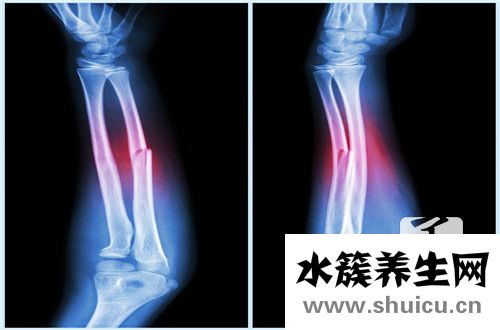

右撓骨遠端骨折在生活當中比較常見,占總的骨折大約1/10左右.多見一些中老年人,尤其是老年女性,因為骨質疏松的原因,很可能發生這個部位發生骨折,相對來說是比較嚴重的,因為發生骨折以后會導致脹痛等現...